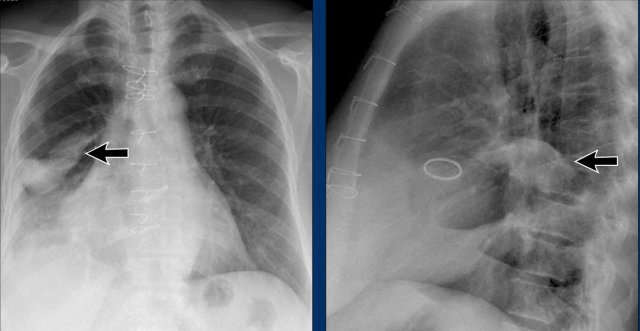

Left Atrial Enlargement

- Patient with a history of chronic mitral valve disease and valve replacement.

- Extreme dilation of the LA leads to bulging of both the right upper cardiac contour (black arrows) and posterior heart border on lateral view (blue arrow).